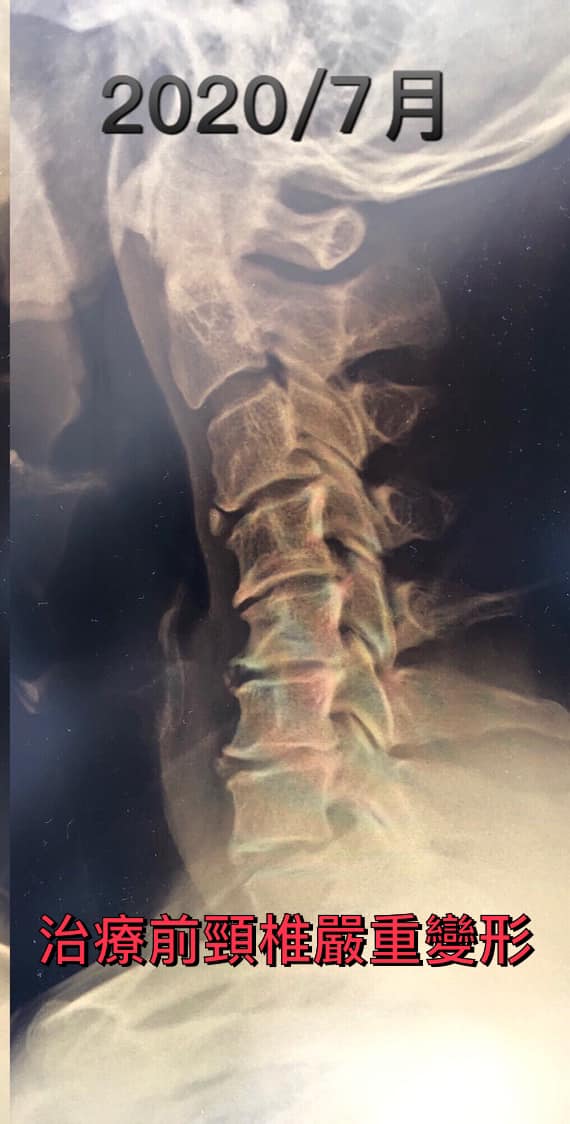

Cervical Spine Treatment Cases 頸椎治療案例 #特殊案例頸椎手術後又再度突出案例 #感謝台中劉大哥熱情見證 #親自手捏醫師娃娃公仔... 2020.11.18 #頸椎病居然會導致手快速萎縮 #脊髓型頸椎病案例 #感謝高雄王大哥熱情見證 #頸椎整合... 2020.11.13 #神經根型頸椎病讓人痛到無法入眠 #感謝新店陳小姐熱情見證 #患者的疼痛日誌讓人感動 ... 2020.11.11 #左邊膏肓長期刺痛案例原來是頸椎病 #之前一直當作肩關節問題處理沒效 #高濃度葡萄糖... 2020.11.03 #腰椎整合醫案逆轉勝 #曾經大痛到無法走路 #坐骨神經痛就是那們痛 #感謝桃園蘆竹張小... 2020.10.29 #特殊案例之味覺錯亂 #原本香甜奶油車輪餅患者覺得酸臭 #按照頸椎病治療五次後突然味... 2020.10.27 頸椎病產生的嚴重交感神經症狀 治療前後比對 2020.10.23 #等待快一年的頸椎受傷醫案追蹤 #頸椎脊髓損傷導致左邊手麻合併下肢無力患者 #前後一... 2020.10.14 #最複雜多變最痛苦難受的頸椎病 #多年的胸悶與心悸伴隨呼吸困難 #交感神經型頸椎病 #... 2020.10.13 #頸椎曲線弧度非常重要 #頸椎弧度有可能逆轉嗎 #短短三個月時間看到效果 #患者超認真... 2020.10.09 #打壘球居然腳不聽使喚跑不起來 #更恐怖的是勉強跑起來還無法剎車 #洗頭往後仰身體背... 2020.10.07 #疼痛三年頸椎病患者親手寫下治療紀錄 #交感神經型頸椎病 #症狀錯綜複雜 2020.10.02 #困擾四年多胸悶手麻頭暈醫案 #一切原因居然是頸椎出問題 #交感神經型頸椎病症狀錯綜... 2020.09.11 #交感神經型頸椎病引起的耳鳴 #耳鳴將近八個月終於得到重大改善 #曾經耳鳴到無法睡覺... 2020.08.22 #感謝板橋蘇先生熱情見證 #神經根型頸椎病卡壓 #曾痛痛到左手無法騎單車撥桿 #麻脹刺... 2020.08.04 ← 上一頁 4 5 6 7 8 下一頁 →